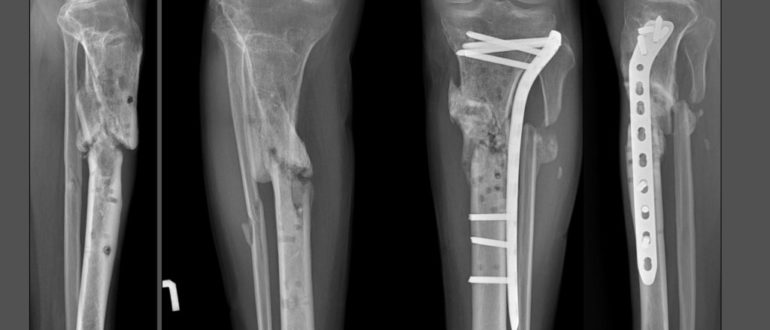

В зависимости от клинической картины, остеосинтез плечевого сустава может быть экстрамедуллярным (с применением пластин) или интрамедуллярным (с использованием спиц). Эти две разновидности операций относятся к группе внутренних, то есть погружных. Для фиксации отломков в этом случае могут использоваться винты, спицы, штифты, пластины, проволока. Внешний (чрескожный) вариант – это установка аппаратов внешней фиксации, самый известный – аппарат Илизарова.

Операция проводится при поперечных переломах костей с достаточным объемом костномозговой полости. Для более прочной фиксации используют штифты с отверстиями для винтов, которые проводят через кость. Это БИОС, то есть блокированный интрамедуллярный остеосинтез. Также используются самоблокирующиеся штифты Fixion. Они позволяют сделать операцию максимально быстро и используются даже при оскольчатых переломах.

Операции с использованием пластины при переломе плеча

Это накостный вариант хирургического вмешательства. Титановые пластины, устанавливаемые в плечо, различаются по длине, ширине, толщине и форме, что позволяет подобрать оптимальный вариант. К кости пластина крепится винтами. Передовая разработка – фиксаторы с угловой и полиаксиальной стабильностью. В отверстиях пластин и головках винтов есть резьба, за счет этого шляпки винтов фиксируются очень прочно, повышая стабильность костного синтеза.

Аппараты внешней фиксации (чрескожная методика)

Методика позволяет репозиционировать и тщательно зафиксировать отломки, не обнажая область перелома.

Ее суть – проведение через костную ткань стержней или спиц, фиксирующихся снаружи в специальном аппарате. Сейчас есть монолатеральные, циркулярные, секторные, полуциркулярные, билатеральные и комбинированные аппараты. Предпочтение чаще отдается стержневым моделям. Использование внешних фиксаторов – незаменимый способ лечения высокоэргичных травм, например минно-взрывных, огнестрельных, которые сопровождаются значительными повреждениями как костей, так и мягких тканей. Периферическое кровоснабжение конечности должно быть сохранено.